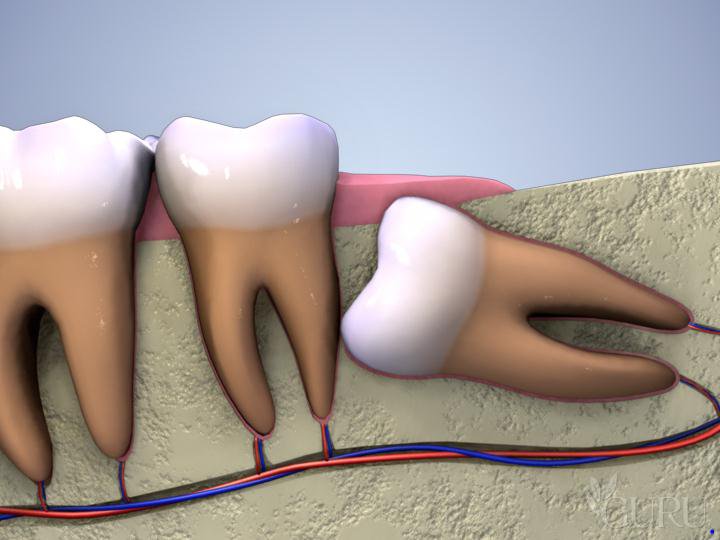

Việc mọc răng khôn

Răng khôn (răng số 8) khi mọc lệch, mọc ngầm thường tạo ra các khe hở với răng số 7. Thức ăn dễ dàng mắc kẹt tại đây nhưng rất khó để làm sạch. Điều này dẫn đến tình trạng viêm lợi trùm, khiến nướu quanh răng khôn sưng to, có mủ và gây ra những cơn đau đầu dữ dội. Đây là một dạng sưng mộng răng đặc thù cần được can thiệp y khoa sớm.

Điều trị tủy hoặc nhổ răng khôn

Trong trường hợp sưng mộng răng là hệ quả của viêm tủy hoặc răng khôn mọc lệch, bác sĩ sẽ tiến hành lấy tủy răng hoặc phẫu thuật nhổ răng khôn để loại bỏ tận gốc ổ viêm, ngăn ngừa bệnh tái phát.

- Xử lý răng khôn mọc lệch: Chủ động thăm khám và nhổ bỏ các răng khôn mọc lệch hoặc mọc ngầm. Những vị trí này tạo ra các túi lợi trùm, là nơi tích tụ thức ăn thừa gây viêm nhiễm cấp tính và sưng mộng răng thường xuyên.